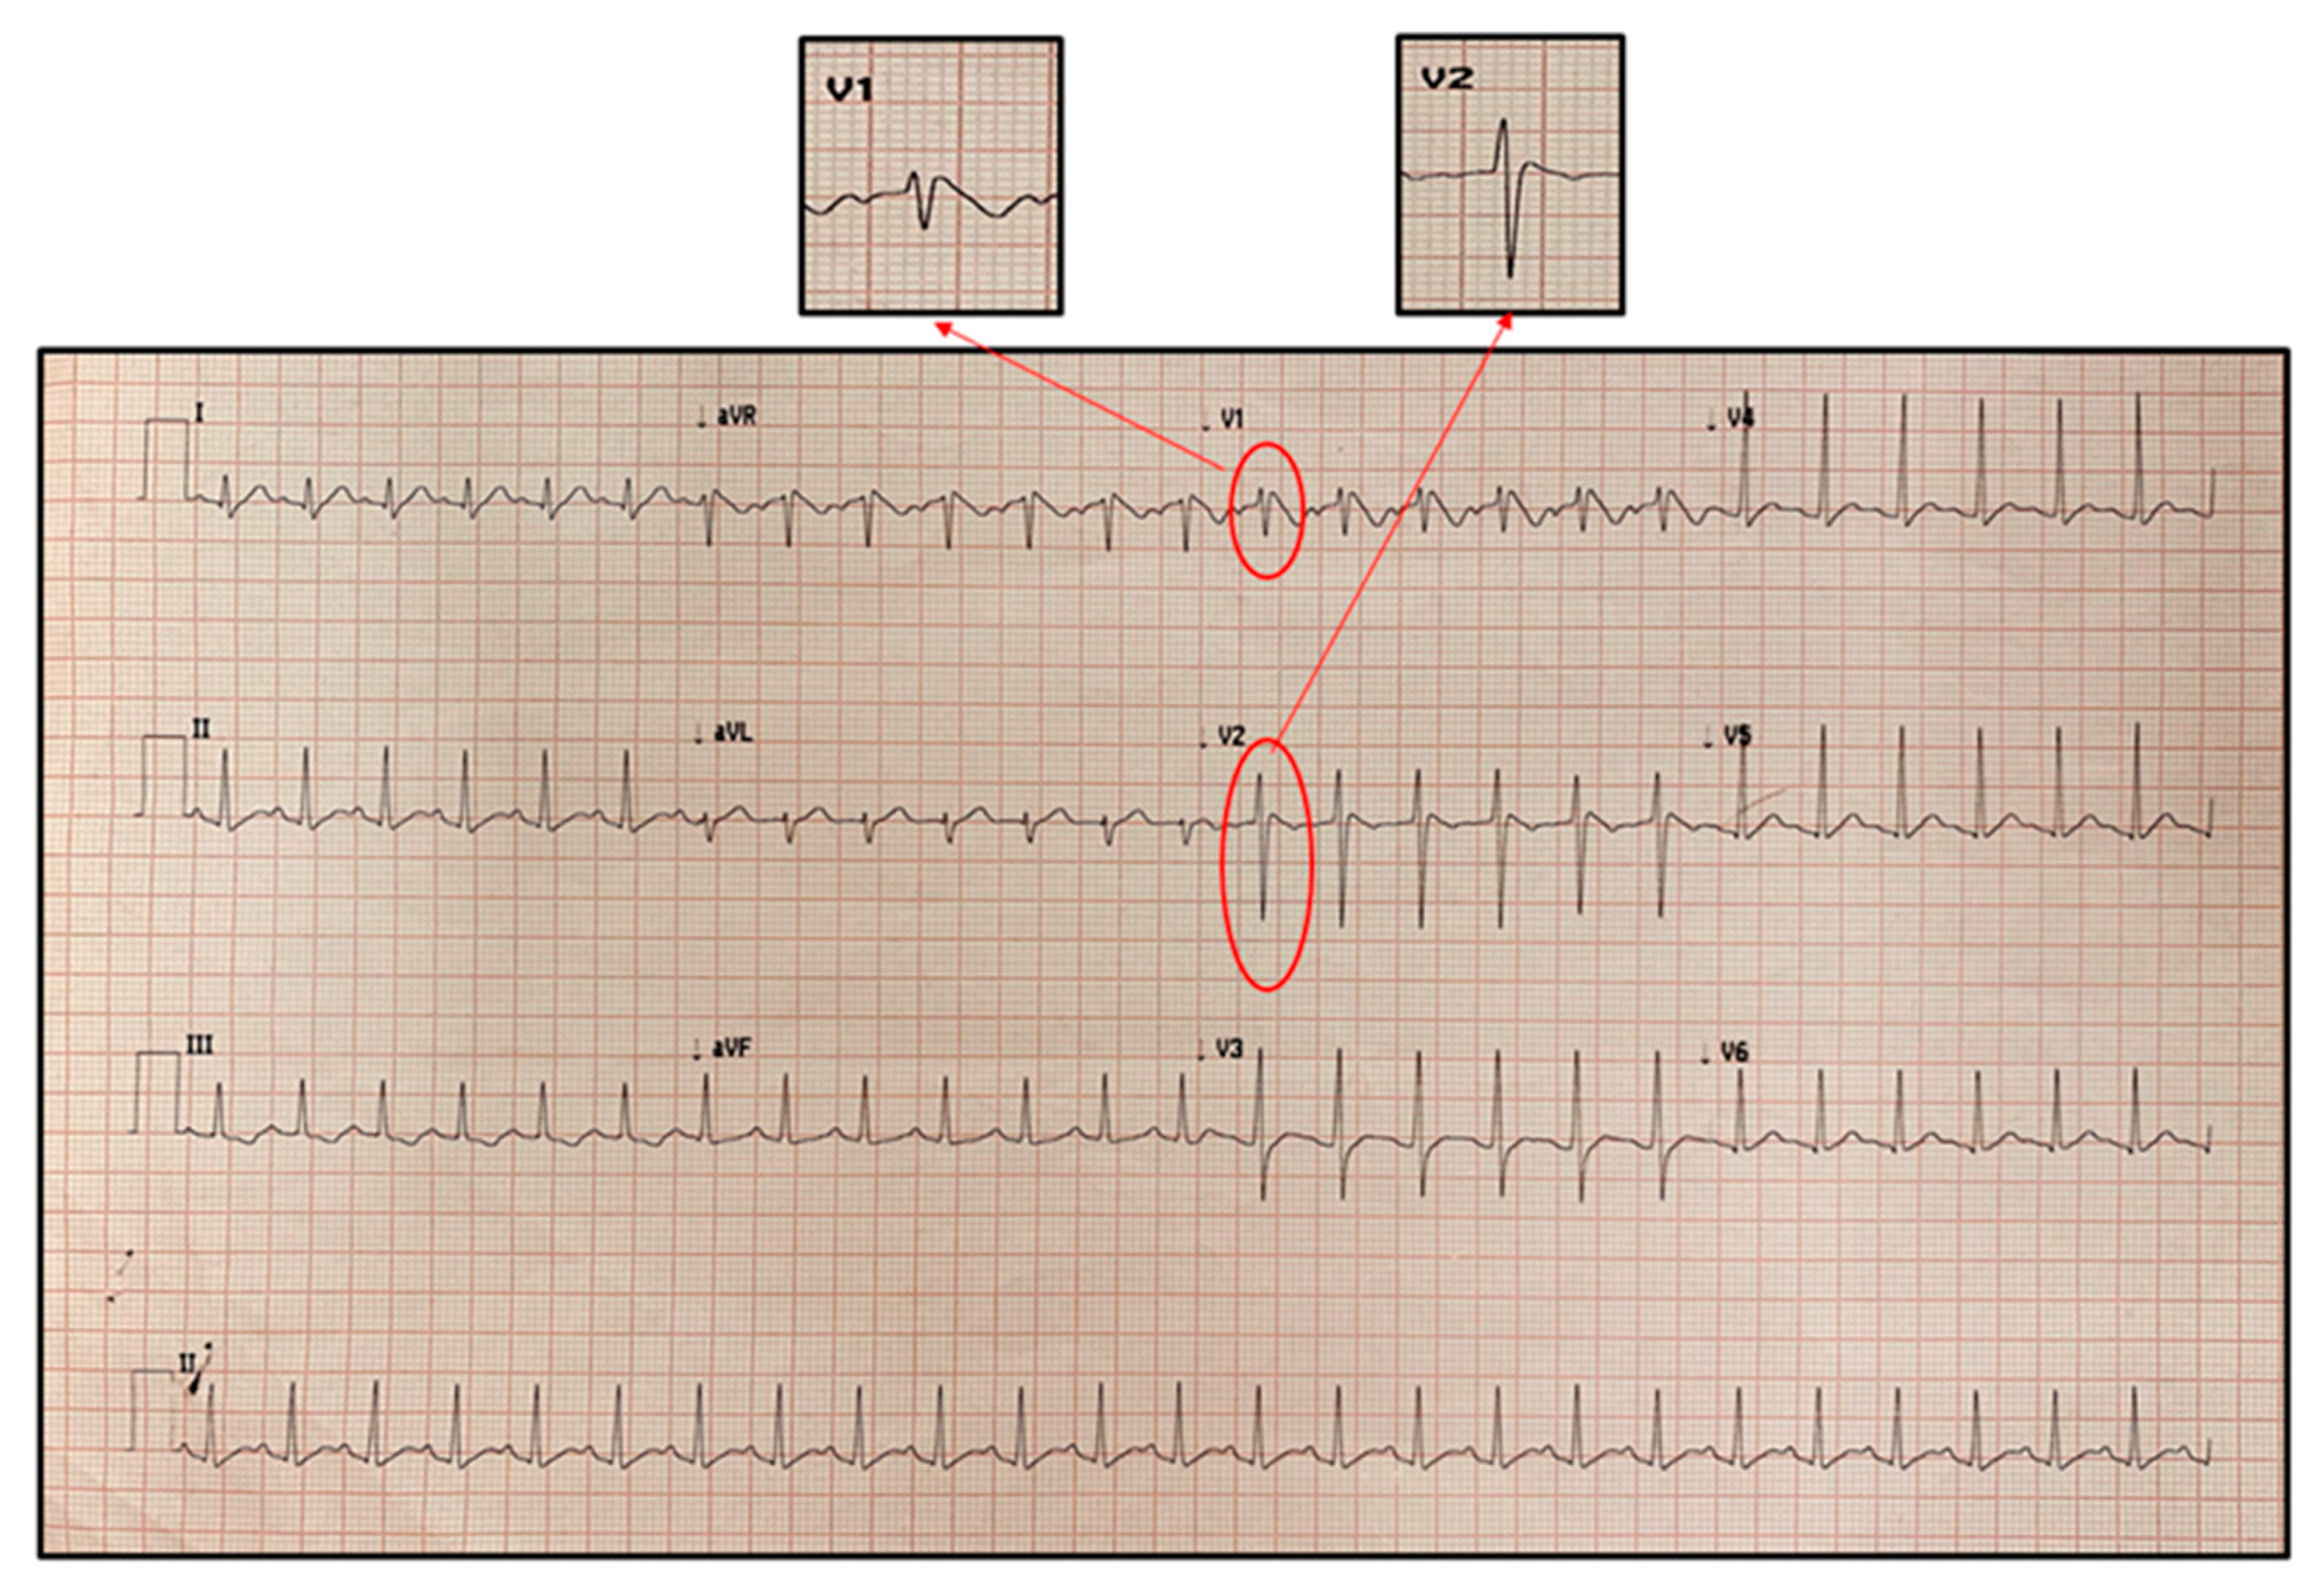

Brugada Pattern in a Child with Severe SARS-CoV-2 Related Multisystem Inflammatory Syndrome

2. Case Report